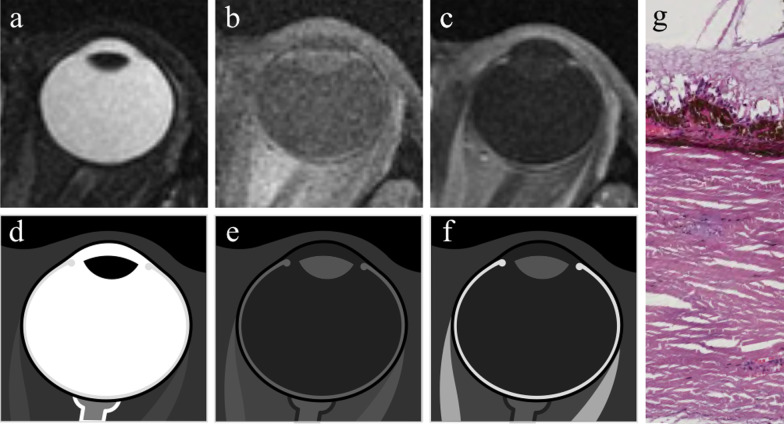

Fig. 6.

MR anatomy of the eye. Axial (a) T2-weighted turbo spin-echo STIR, (b) fat-suppressed T1-weighted, (c) contrast-enhanced fat-suppressed T1-weighted images. d–f Corresponding schematic drawings. (g) Corresponding histological detail illustrating the three-layered wall of the globe: (from outer to inner) sclera, choroid and retina (H&E, original magnification ×200)

The uveal tract (thickness 0.1–0.22 mm at the level of the choroid) displays slightly high signal intensity on T1-weighted images and low signal intensity on T2-weighted images, although on this latter sequence it is partially obscured by the high signal of aqueous and vitreous humor.

The thickness of the retina ranges from 0.056 mm and 0.1 mm [23]. Under physiological conditions, the retina is closely connected to the choroid and cannot be perceived individually.

After contrast media administration the uveal tract and retina demonstrated enhancement on T1-weighted images. Therefore, differently from T1-weighted images, on T2-weighted sequences the different layers cannot be differentiated and the wall of the eye appears as an evenly hypointense line.

When retinal or choroidal detachments occur, then the different layers of the eyeball can be separately detected.

The lens shows a typical biconvex shape and, due to its high protein content, displays intermediate signal intensity on T1-weighted images and low signal intensity on T2-weighted images.

The aqueous humour and vitreous body have a water content greater than 98% and therefore exhibit a water-like signal intensity at MRI, appearing dark and bright on T1- and T2-weighted images, respectively [22, 23, 25, 26].